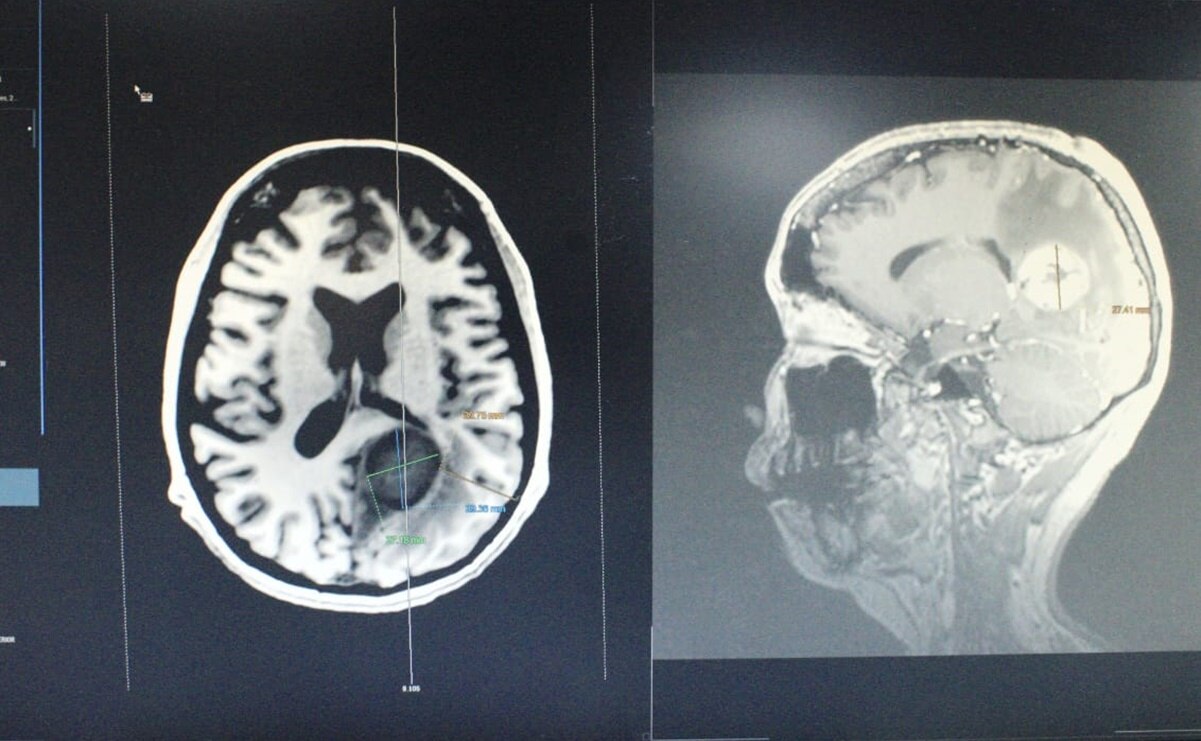

Un grupo multidisciplinario de médicos especialistas del Instituto de Seguridad y Servicios Sociales de los Trabajadores del Estado (ISSSTE) retiraron exitosamente un tumor cerebral maligno del tamaño de un huevo a una mujer de 34 años. La operación se realizó en del Centro Médico Nacional (CMN) “20 de Noviembre”, duró cinco horas, y participaron cinco especialistas, un anestesiólogo y dos enfermeras especialistas, que lograron extirpar con éxito el tumor que se localizaba del lado izquierdo en la zona profunda del cerebro. El diagnóstico de la paciente, cuya identidad no fue revelada, era una metástasis de cáncer tipo leiomiosarcoma desarrollado en el corazón. El tumor, informó el ISSSTE comprometía estructuras relacionadas con lenguaje, comprensión, cálculo y función visual. En la intervención de cinco horas se mantuvo a la paciente despierta para monitorear las funciones de su sistema nervioso central y preservarlas, haciéndole preguntas sobre nombres, fechas, sumas o restas en secuencia e indicaciones de mover diferentes partes del cuerpo.

Cuauhtémoc Gil-Ortiz Mejía relató que en tres meses la paciente fue sometida a tres operaciones. Su diagnóstico inicial era ajeno al tumor cerebral, pues lamujer primero fue operada de la vesícula y después sometida a un procedimiento de corazón abierto para retirarle un tumor. Durante la cirugía del corazón, la paciente presentó problemas de lenguaje, y desconocía la parte derecha de su cuerpo, por ello fue valorada en neurocirugía. Se le programó neurocirugía, un procedimiento de alta especialidad, que se realizó el pasado 22 de marzo. Lee también: En el ISSSTE hay déficit de médicos y si hay que traerlos de Cuba o Francia, lo haremos: Pedro Zenteno Suscríbete aquí para recibir directo en tu correo nuestras newsletters sobre noticias del día, opinión, Qatar 2022 y muchas opciones más.